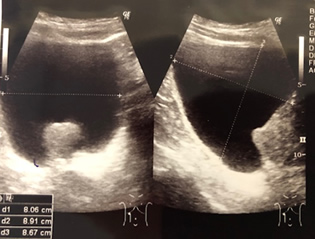

前立腺の大きさを超音波検査で測定します。正常な前立腺の大きさは20ml以下ですので、それ以上の大きさであると前立腺肥大症の疑いがあります。大きくなると左図のように膀胱内に前立腺が突出してくる場合もあります。その他に、勢いよく排尿できているかを調べるために尿流量検査なども行います。